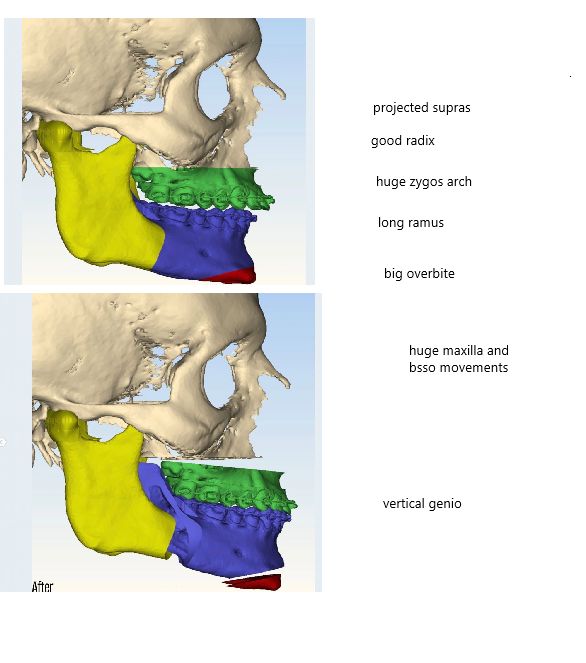

Lets now look at another alfaro case which didnt have equally good ascension, but he still had a sfs.

As we can see from the front he didnt have as much of a overbite or retrusion.

Because he didnt have much recession the lower jaw didnt became more vertically long as it wasnt hidden away behind a huge overbite or deep bite as in gustavos case. But he did a vertical genio which i think was a mistake

lets look at his bones and compare to gustavos: